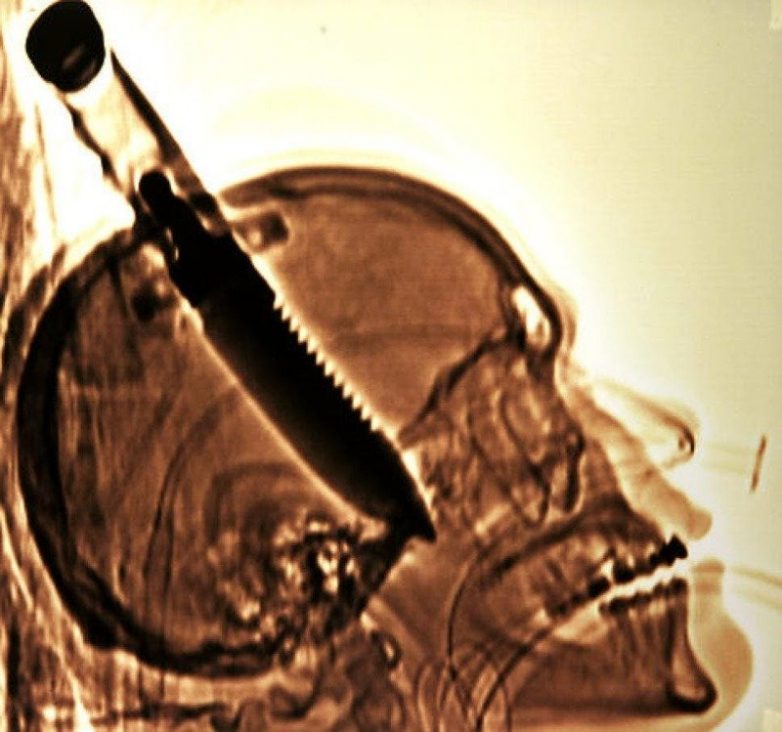

3. Самый большой объект, удаленный из черепа пациента

В 1998 году американца Майкла Хилла ударили ножом в голову и бросили умирать. Это был здоровый нож с 20-сантиметровым лезвием. Врачам удалось спасти мужчину, удалив лезвие из его головы, и этот невероятный рекорд был зафиксирован в Книге рекордов Гиннесса.